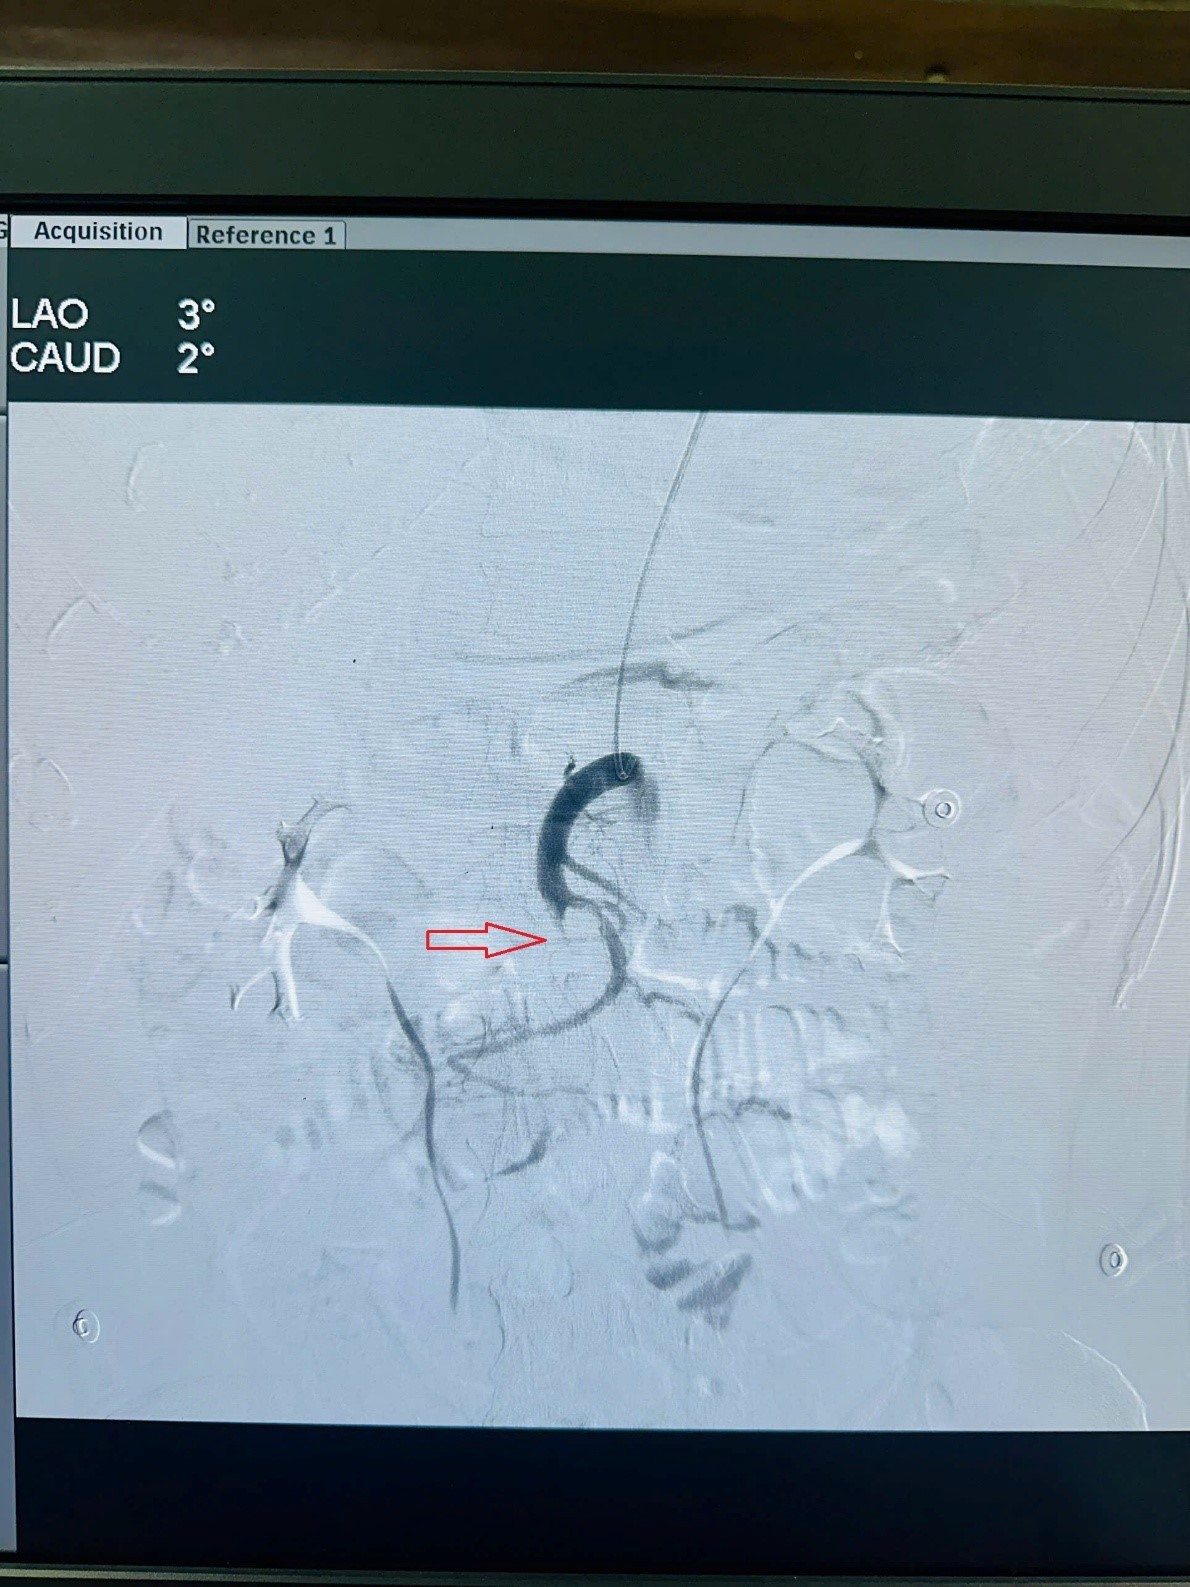

Hình 1: Huyết khối gây tắc phần lớn động mạch mạc treo tràng trên và các

nhánh bên